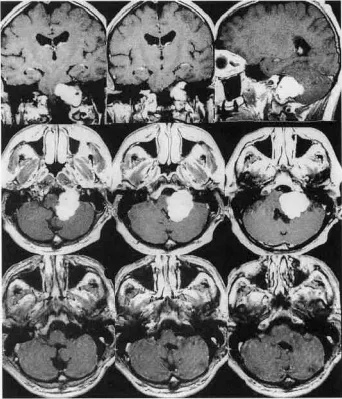

45歲男性,眩暈1年為主訴入院。左側(cè)外展、面、聽神經(jīng)功能障礙。在MRI上(圖1),發(fā)現(xiàn)一個較大的頸靜脈孔腫瘤向顱內(nèi)外延伸。病人選擇巴特朗菲教授手術(shù),教授通過左側(cè)擴大經(jīng)髁入路。腫瘤被完全移除了。組織學(xué)檢查發(fā)現(xiàn)是神經(jīng)鞘瘤。術(shù)后過程平安無事。術(shù)后2年隨訪,腫瘤未復(fù)發(fā)。

術(shù)前MRI顯示左側(cè)頸靜脈孔較大占位,顱內(nèi)外延伸,術(shù)后確診神經(jīng)鞘瘤,術(shù)后2年復(fù)查MRI顯示腫瘤完全切除且沒有復(fù)發(fā)

圖示:術(shù)前MRI顯示左側(cè)頸靜脈孔較大占位,顱內(nèi)外延伸,術(shù)后確診神經(jīng)鞘瘤,術(shù)后2年復(fù)查MRI顯示腫瘤完全切除且沒有復(fù)發(fā)